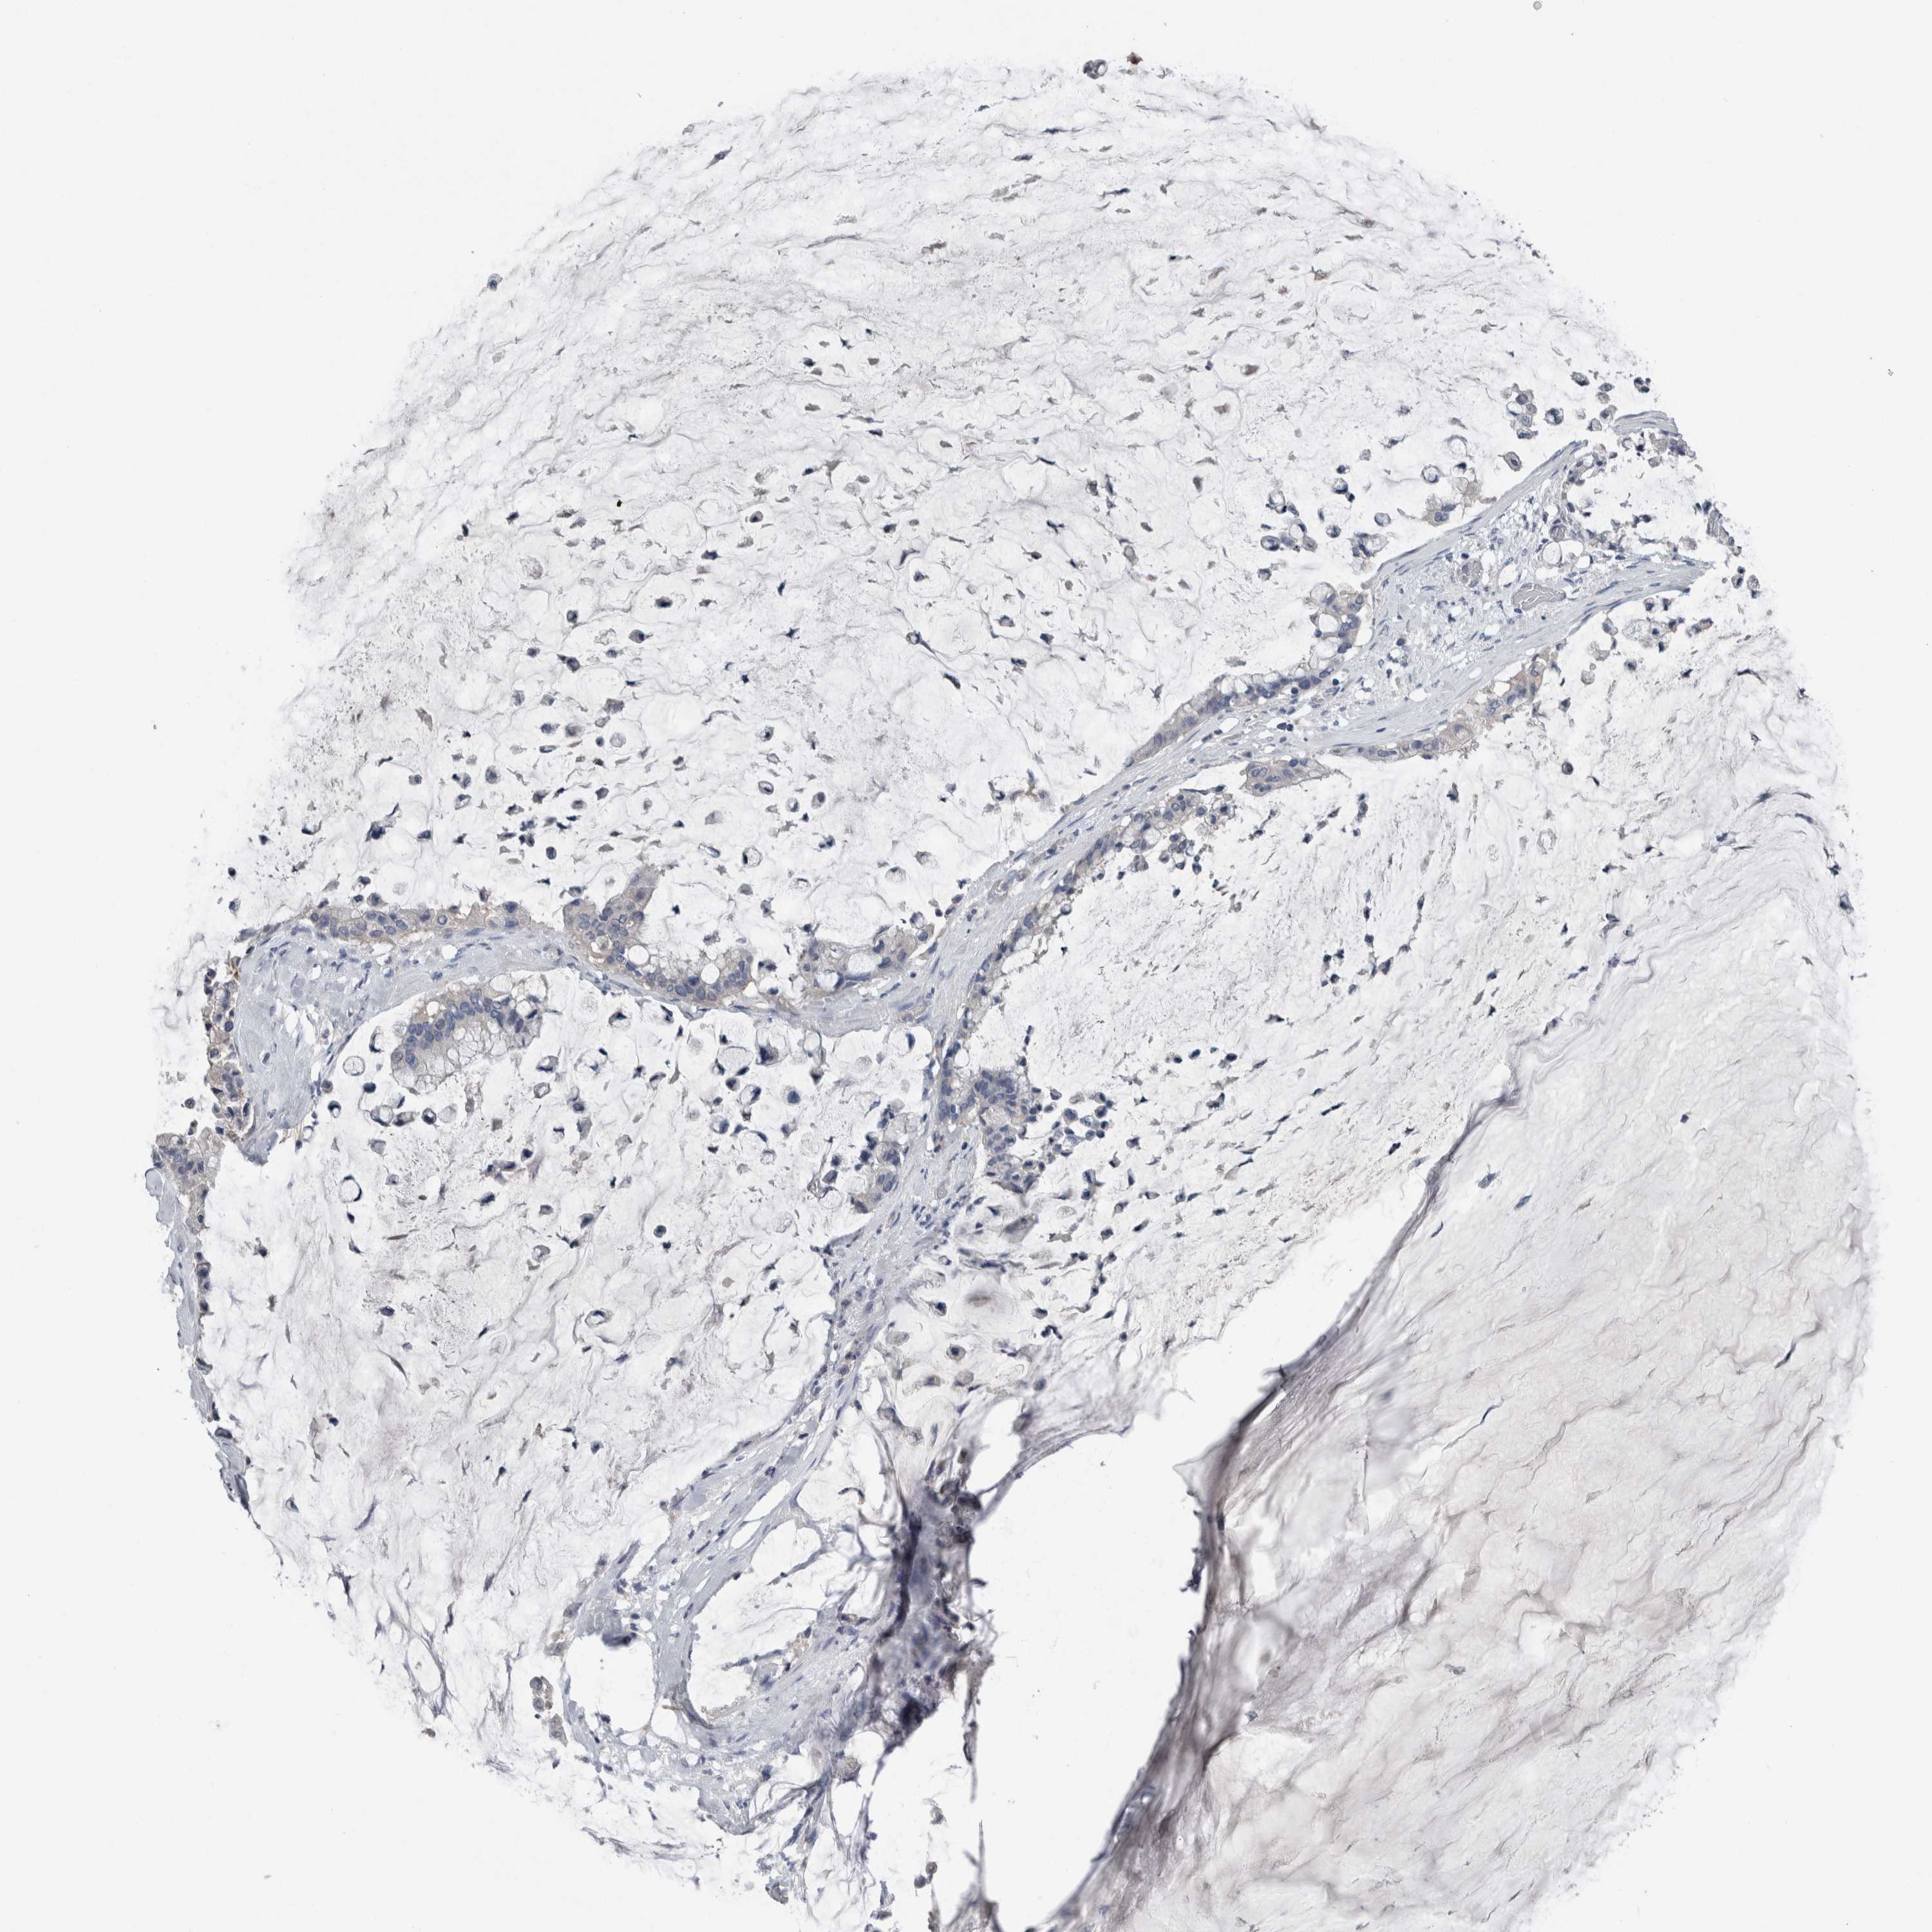

PANCREATIC CANCER - Protein expressioni

A mouse-over function shows sample information and annotation data. Click on an image to view it in a full screen mode. Samples can be filtered based on level of antibody staining by selecting one or several of the following categories: high, medium, low and not detected. The assay and annotation is described here.

Note that samples used for immunohistochemistry by the Human Protein Atlas do not correspond to samples in the TCGA dataset.

Antibody stainingi

Antibody staining in the annotated cell types in the current human tissue is reported as not detected, low, medium, or high, based on conventional immunohistochemistry profiling in selected tissues. This score is based on the combination of the staining intensity and fraction of stained cells.

Each image is clickable and will lead to virtual microscopy that enables deeper exploration of all samples and also displays staining intensity scores, fraction scores and subcellular localization as well as patient and tissue information for each sample.

Antibody HPA024343

Antibody CAB026182

Staining

High

Medium

Low

Not detected

Intensity

Strong

Moderate

Weak

Negative

Quantity

>75%

75%-25%

<25%

None

Location

Nuclear

Cytoplasmic/membranous

Cytoplasmic/membranous,nuclear

Adenocarcinoma, NOS